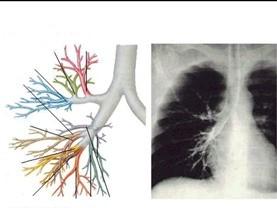

右主支气管的特点见图 ( )A、长、粗、倾斜B、无上述特点C、短、细、垂直D、短、细、倾斜E、粗、短、垂直

问题 右主支气管的特点见图 ( )

选项 A、长、粗、倾斜 B、无上述特点 C、短、细、垂直 D、短、细、倾斜 E、粗、短、垂直

答案 E